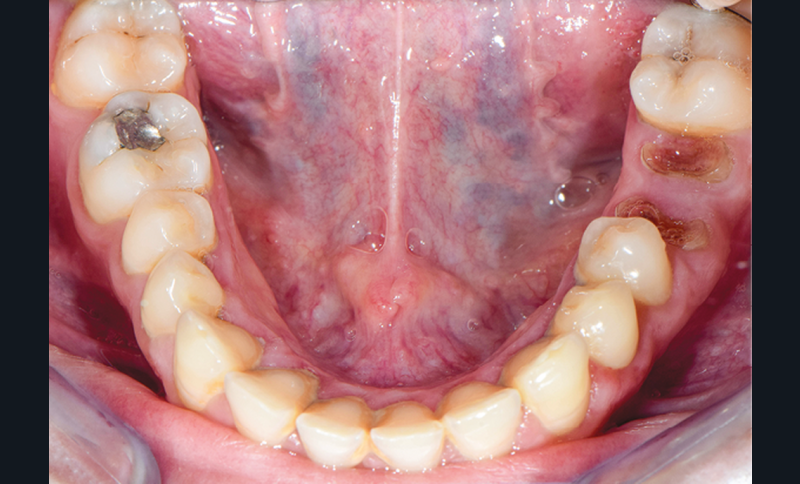

À l’examen endobuccal (fig. 1), une inflammation marginale et papillaire sur un parodonte de biotype fin est visible. Une gingivite généralisée induite par la plaque bactérienne est donc diagnostiquée.`

La ligne du sourire est inversée, malgré une perception atténuée par la présence de deux couronnes à armature zircone sur 11 et 21 réalisées une dizaine d’années auparavant. On note une irrégularité et une asymétrie de forme des festons gingivaux, ainsi qu’une dysharmonie de forme des incisives et canines quant à leur proportion.

L’arcade maxillaire présente des signes d’usure érosive caractéristiques d’attaques acides : surface lisse, de couleur satinée, présence d’un pourtour d’émail sain en regard du sulcus, et effacement des morphologies dentaires telles que la disparition des cuspides palatines des prémolaires et de la 16. En revanche, 26 et 46 ne présentent aucun problème d’usure. La patiente ne rapporte pas de signes d’hyperesthésie dentinaire. Par ailleurs, la dimension verticale d’occlusion (DVO) étant conservée, la patiente présente une usure majeure compensée par l’égression dentaire (ce qui montre une évolutivité lente).

L’arcade mandibulaire présente un pseudo-édentement de classe III de Kennedy (36 à l’état de racines).